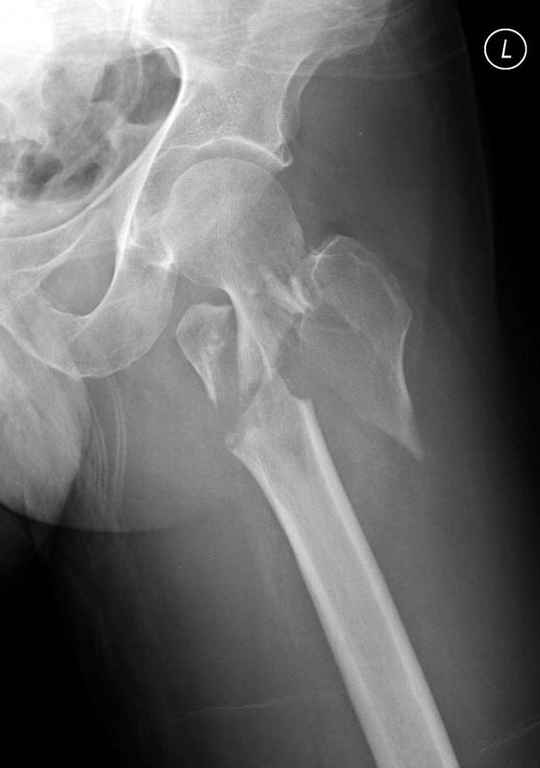

Re: оскольчатый чрезвертельный перелом

Не солидно экономить на пленке, это не делает чести презентации. Такие ограниченные нестандартные снимки приводят к тактическим ошибкам.

Предугадать распространение линий перелома при чрезвертельных и оскольчатых переломах трудно, поэтому для принятия правильного решения рекомендуется Компьютерно Томографические исследование.

При отсутствии КТ, снимок на вытяжении поможет увидеть общую картину расположения отломков, особенно потенциальные места введения импланта. Риск раскола в этом случае огромный, поэтому больной должен быть дообследован.

Здесь пара похожих случаев.